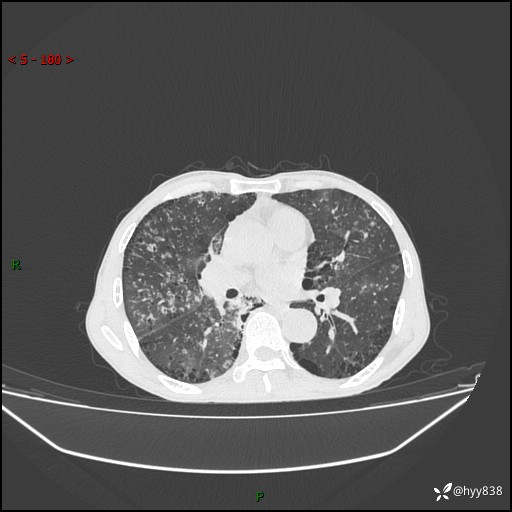

胸部CT平扫